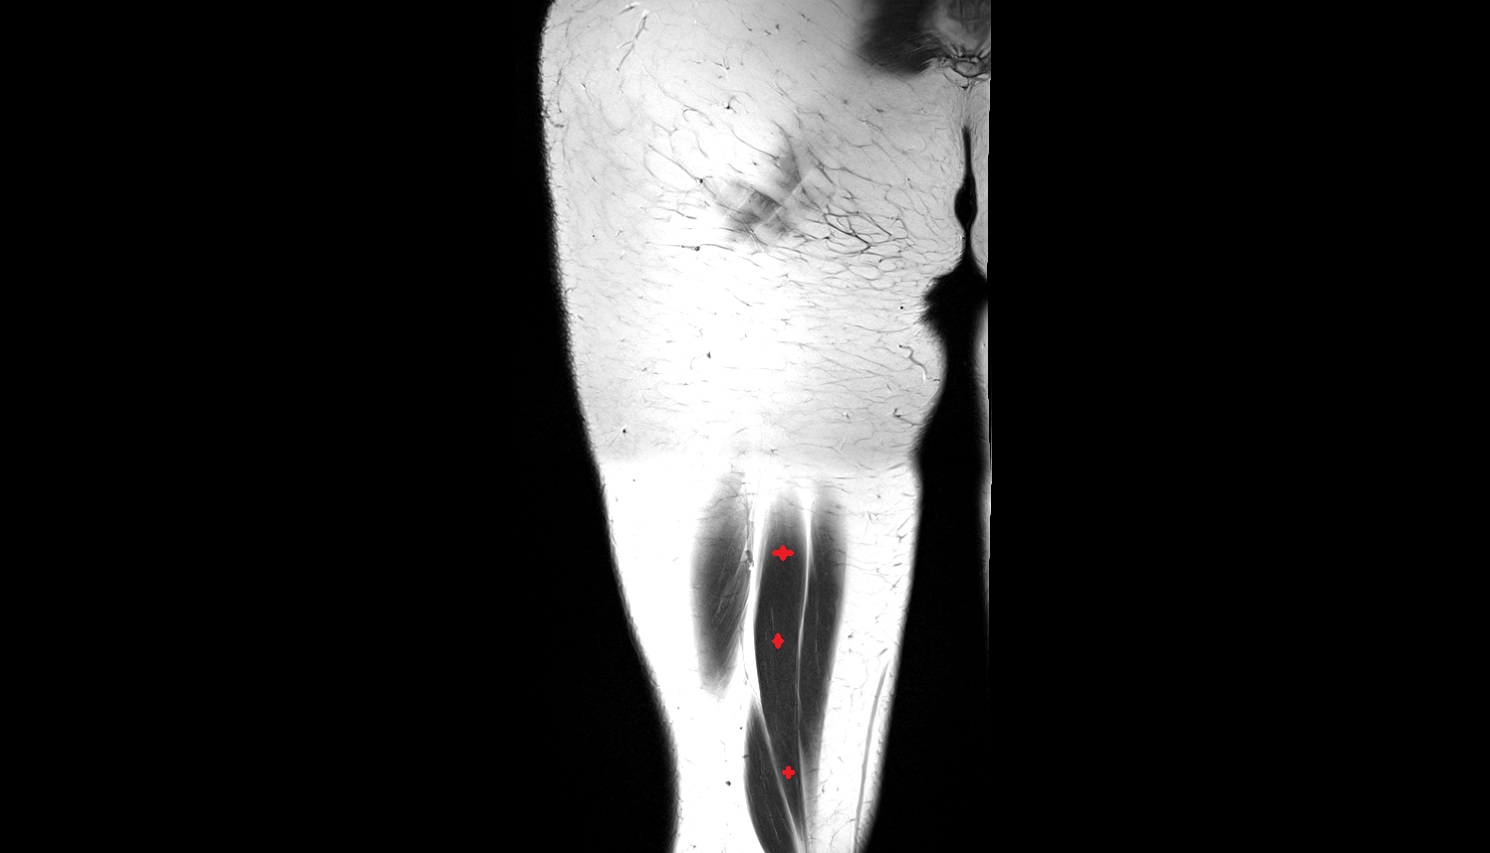

- Plantaris muscle

- Lateral head of gastrocnemius muscle

- Medial head of gastrocnemius muscle

- Gastrocnemius muscle

- Popliteus muscle

- Soleus muscle

- Extensor digitorum longus muscle

- Tibialis anterior muscle

- Fibularis longus muscle (peroneus longus muscle)

- Tibialis posterior muscle

- Flexor digitorum longus muscle

- Flexor hallucis longus muscle